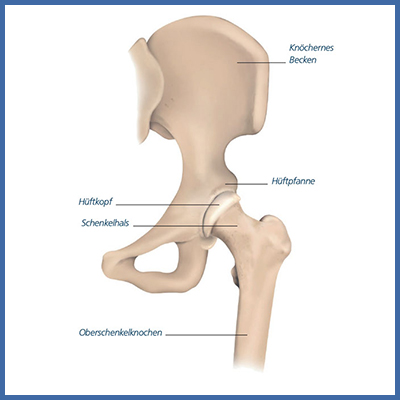

Als eigentliches Kugelgelenk ist es simpel aufgebaut und besteht aus zwei knöchernen Bestandteilen, dem Beckenknochen und der Gelenkspfanne, in die der Oberschenkelkopf idealerweise perfekt hineinpasst. Mit Hilfe von stabilisierenden Bändern und dem harmonischen Zusammenspiel einer Vielfalt von Muskeln ist es uns möglich sich auf verschiedene Arten zu bewegen; sei dies gehen, laufen oder springen.